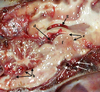

Label A-F

A = temporais muscle

B = pterygoid muscle

C = body of the mandible

D = zygomatic salivary gland

E = zygomatic arch

F = periorbita